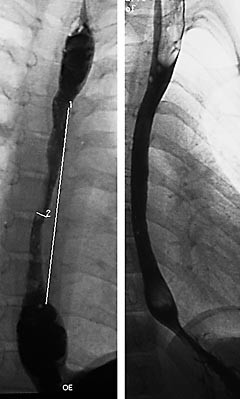

Pasient 3 . Seks år gammel gutt med Downs syndrom, som var operert for atrioventrikulær kanal og hadde sekundær mitralinsuffisiens. Han ble behandlet for obstruktiv lungesykdom med inhalasjonssteroider og betaagonister, og var hyppig innlagt i sykehus på grunn av residiverende luftveisinfekjoner, spesielt pneumonier. Fra seks måneders alder hadde han økende dysfagi av mat med fast konsistens. Grøt og væske passerte derimot uten problemer. Hematemese og melena ble observert gjentatte ganger. Vekt i forhold til høyde var ved 10. percentil. Ved 24-timers pH-registrering kunne det påvises markert refluks med refluksindeks på 53,1 %. Lengste episode varte 89 minutter. Oesophagusmanometri viste reduserte amplituder av de peristaltiske bølger. Endoskopi viste en markert striktur (fig 2a, b). Han behandles fortsatt med cisaprid, omeprazol og gjentatte blokkinger etter behov. Nissens fundoplikasjon planlegges utført.